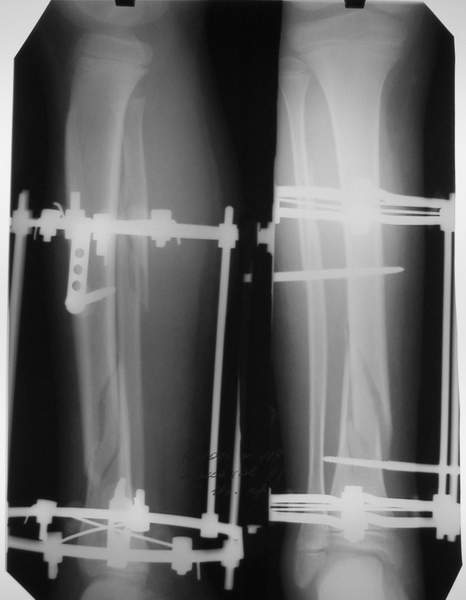

Под рукой прилагаемый пример. Как видите, "стриптиз-аппарат" (шутка проф. З.К.Башурова): 3 кольца-2 кольца-2 полукольца. В случае, который представил Евгений, характер повреждения позволил бы сразу использовать аппарат на основе 2 колец; в крайнем случае прокс. опора м.б. демонтирована сразу после репозиции.

В аттачтах №№ 1 и 2 - примеры, когда 2 кольца не позволили послеоперационно

исправить смещение фрагментов большеберцовой (по ширине и вальгусное).

А казалось бы (#2) - поиграй на штангах и все влетит.

1

1a